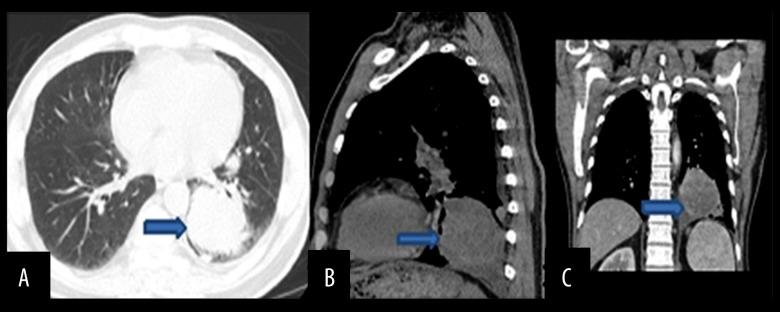

BACKGROUND Sarcomatoid carcinoma is a rare, aggressive, malignant cancer composed of sarcoma and sarcoma-like components, and can occur in different organs such as the thyroid gland, bone, skin, breast, pancreas, liver, urinary tract, and lung. Pulmonary sarcomatoid carcinoma accounts for only a small percentage of lung cancers and has histological variants that include pleomorphic carcinoma, giant cell carcinoma, spindle cell carcinoma, carcinosarcoma, and pulmonary blastoma. CASE REPORT Here, we present a case of sarcomatoid carcinoma in a 63-year-old HIV-positive Hispanic male who presented with back pain, dry cough, and weight loss. A CT scan of his chest showed an ovoid mass in the lower lobe of the left lung, and an MRI of the spine showed a left lateral paraspinal soft tissue mass causing central canal stenosis and mild cord compression. The patient underwent laminectomy and resection of the spinal mass. A transthoracic needle biopsy of the lung and spinal masses had similar histopathology, and were indicative of sarcomatoid carcinoma. CONCLUSIONS We report a rare case of sarcomatoid carcinoma involving both the lung and spinal cord in the same patient. Sarcomatoid carcinomas of the lung have poor prognosis and are aggressive cancers. Moreover, our case also had the co-occurrence of HIV and sarcomatoid carcinoma.

肉瘤样癌是一种罕见的侵袭性恶性肿瘤,由肉瘤和肉瘤样成分组成,可发生于不同器官,如甲状腺、骨骼、皮肤、乳腺、胰腺、肝脏、泌尿道和肺部。肺肉瘤样癌仅占肺癌的一小部分,具有多种组织学变异型,包括多形性癌、巨细胞癌、梭形细胞癌、癌肉瘤和肺母细胞瘤。病例报告:在此,我们报告一例63岁的HIV阳性西班牙裔男性肉瘤样癌患者,该患者出现背痛、干咳和体重减轻症状。胸部CT扫描显示左肺下叶有一个椭圆形肿块,脊柱MRI显示左侧椎旁软组织肿块,导致中央管狭窄和轻度脊髓受压。患者接受了椎板切除术和脊柱肿块切除术。对肺部和脊柱肿块进行的经胸针吸活检具有相似的组织病理学表现,提示为肉瘤样癌。结论:我们报告了一例罕见的同一患者同时发生肺和脊髓肉瘤样癌的病例。肺肉瘤样癌预后较差,是侵袭性癌症。此外,我们的病例还同时存在HIV和肉瘤样癌。